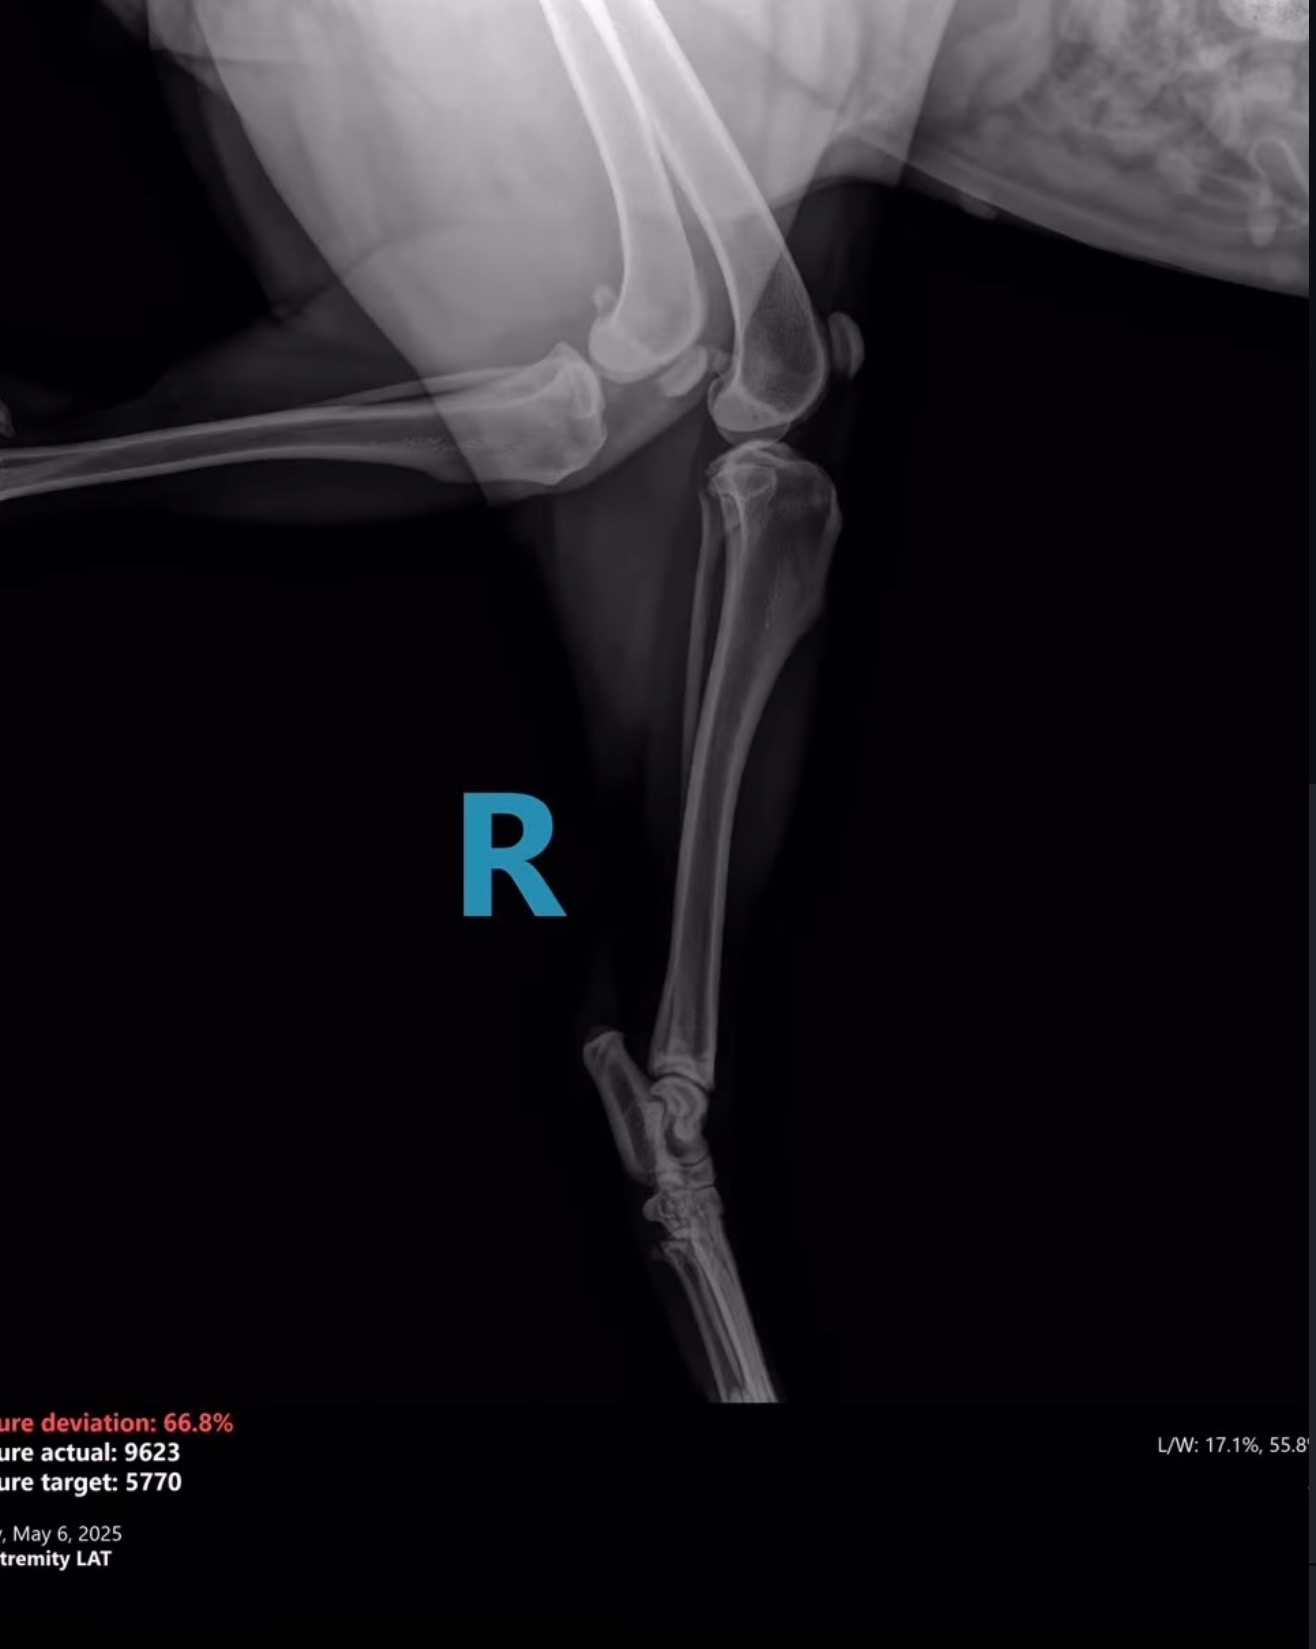

On Monday, a Good Samaritan found Harper in Dekalb County broken and in urgent need of medical attention. Unfortunately, their car broke down on the way to DCAS, and Gwinnett County kindly took her in. Harper arrived without a microchip and the shelter has been unable to locate an owner. We are unsure what caused her injuries exactly, but they are severe.

Harper has suffered multiple fractures on the left side

of her pelvis, including:

1. Left ischium

2. Left acetabulum

3. Crushed left ilial wing

4. Suspected fracture at the left sacroiliac (SI) joint

We’ve attached her kennel X-rays, and a short video to help you get to know her better.